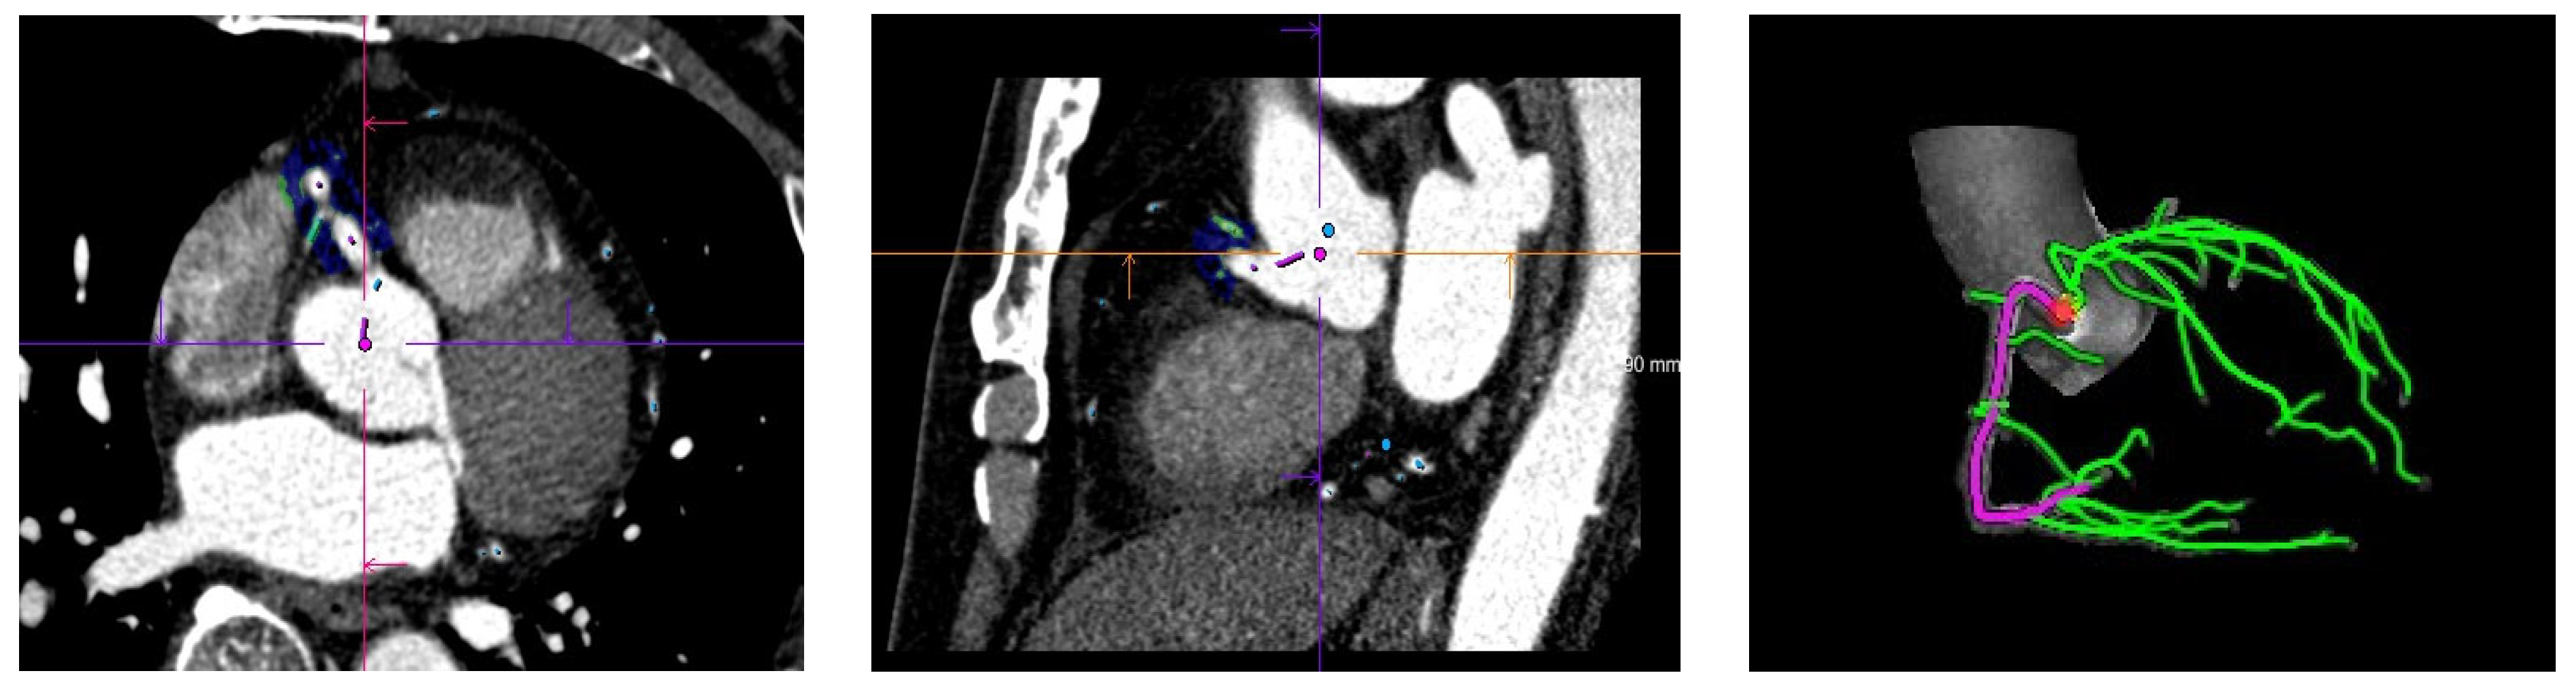

2.4. CCTA Image Analysis

2.5. Measurement of the FAI Value of Fat around the Coronary Artery